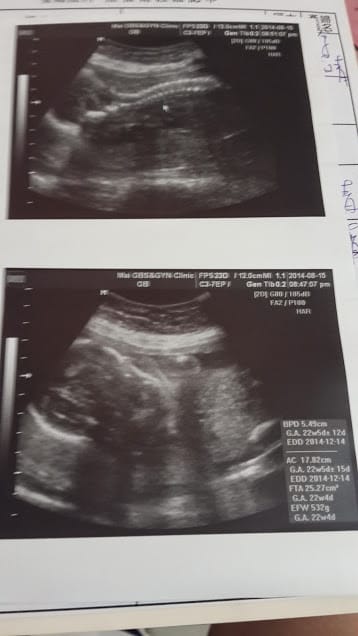

終於捱到第二次產檢了! 肚子大到視覺感已…